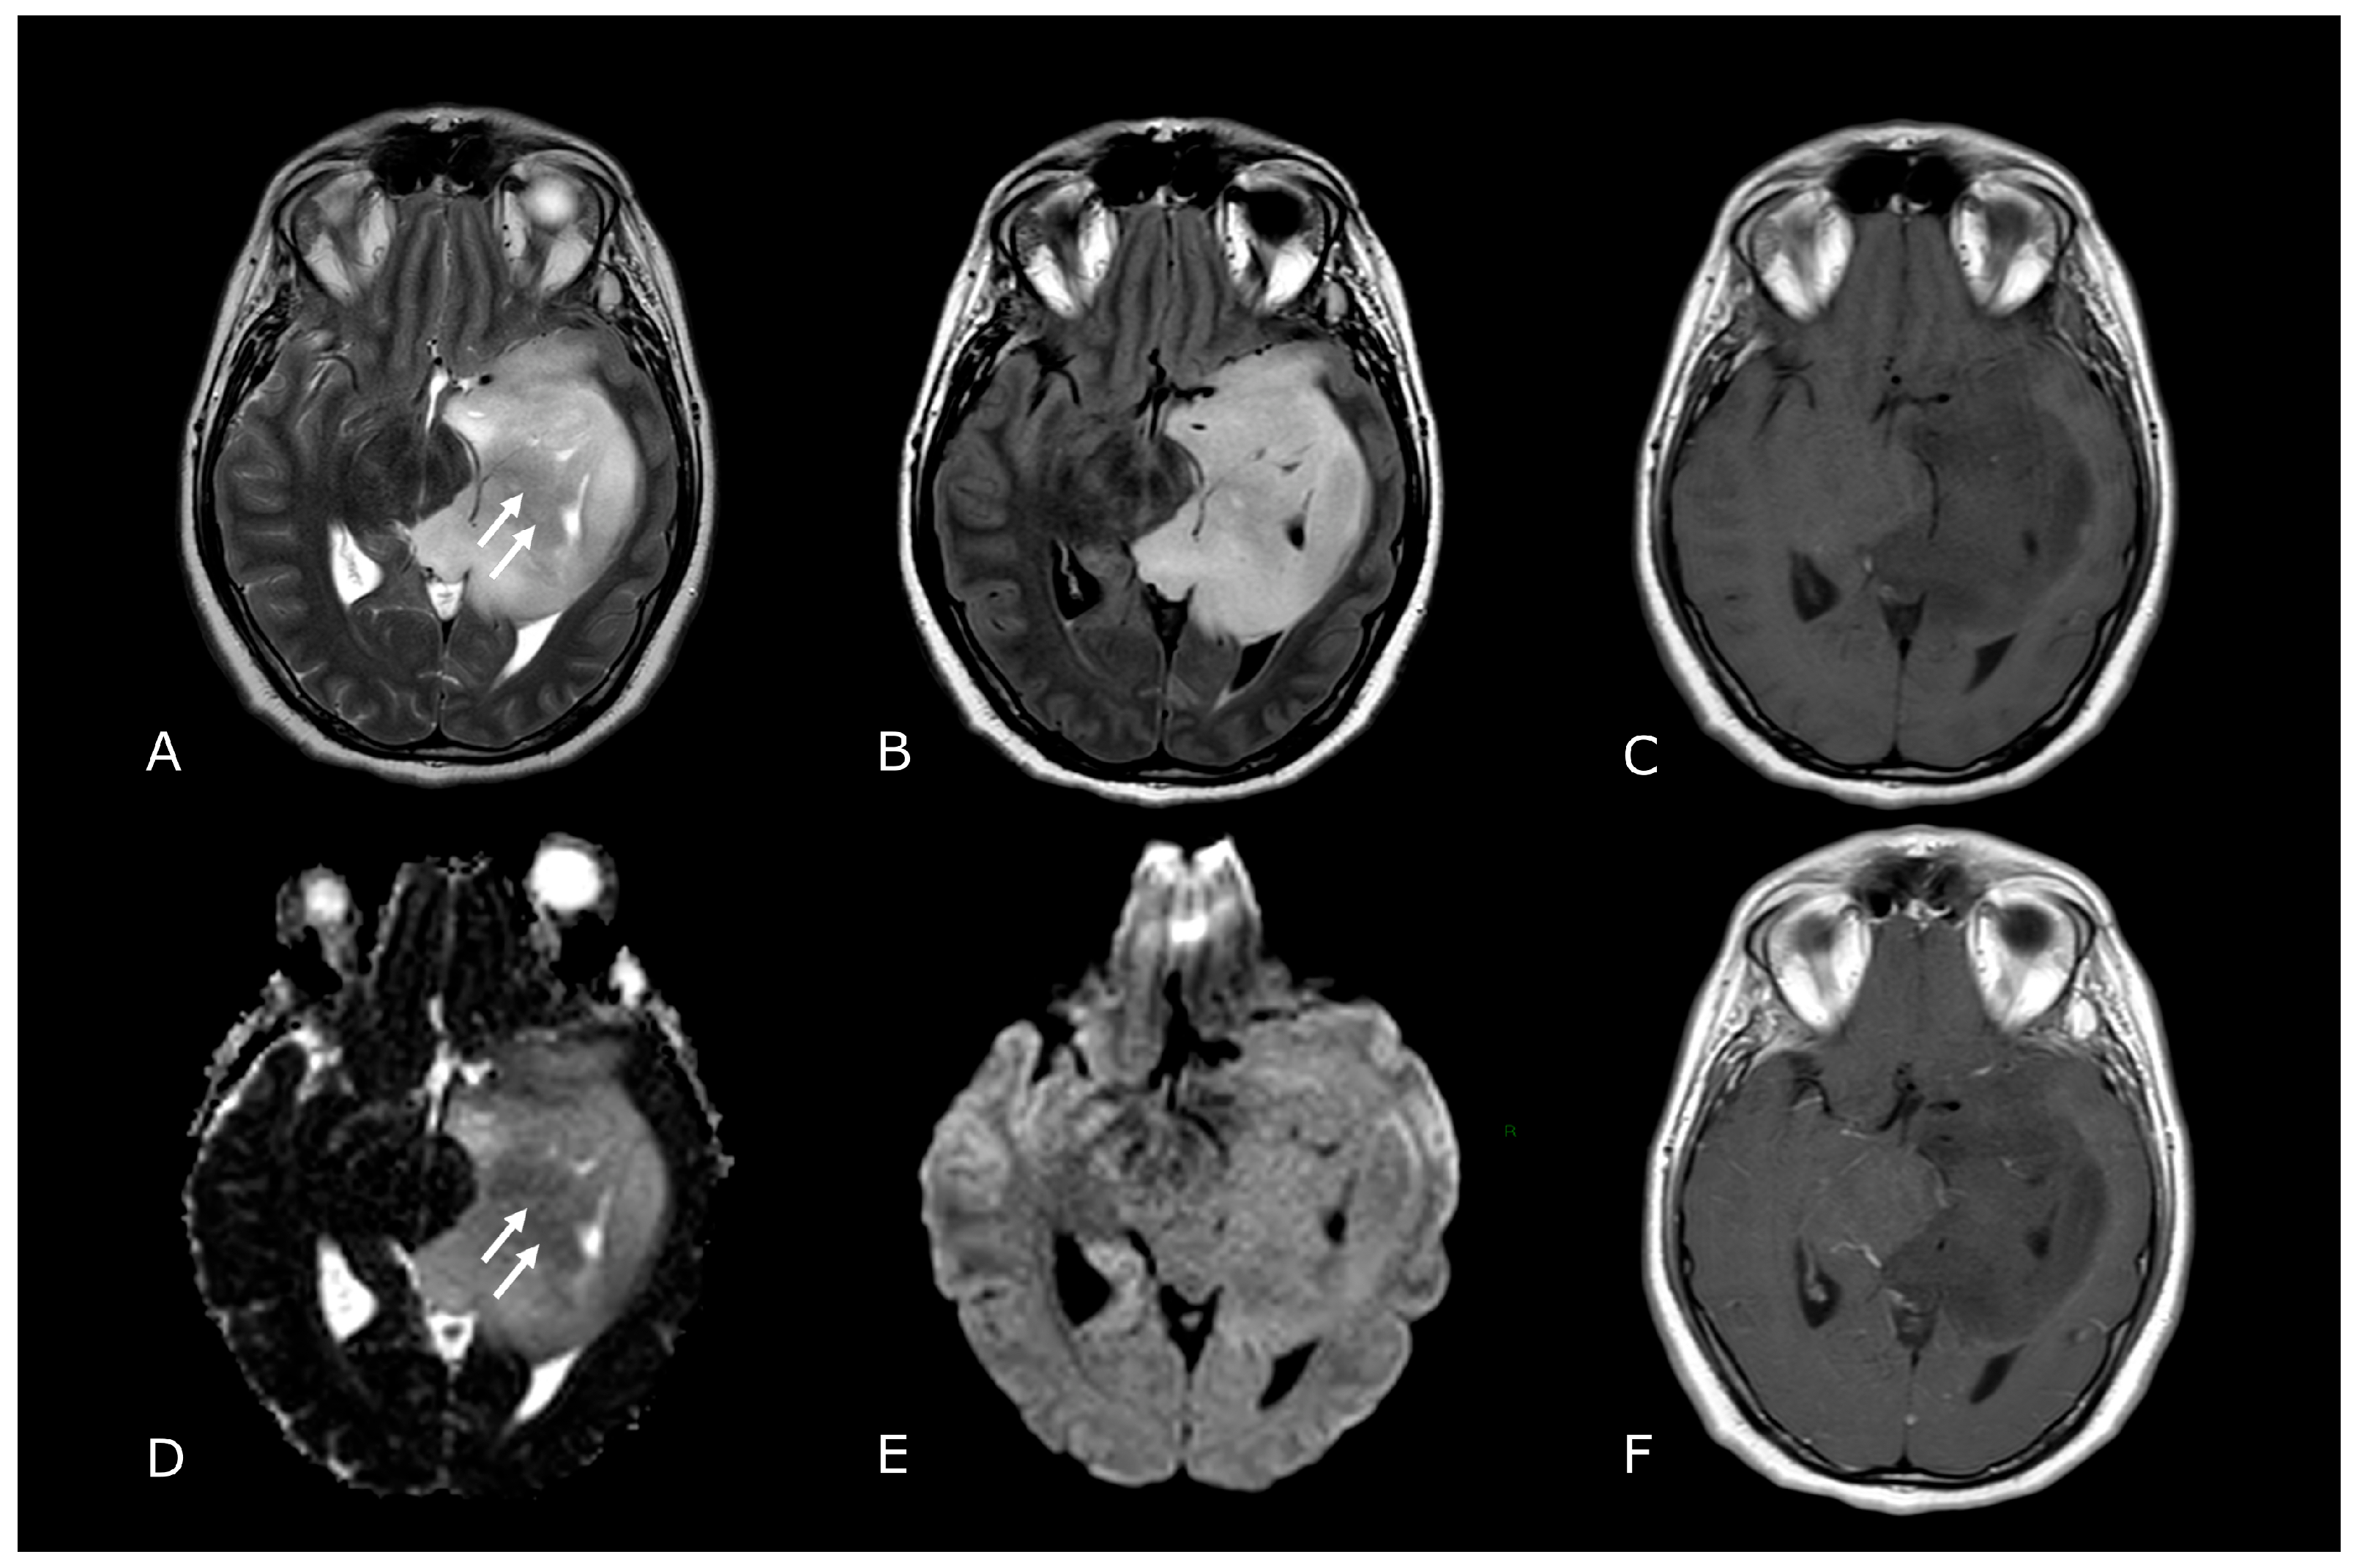

Figure 1.

Morphological sequences: tumor cellularity. Morphological sequences: tumor cellularity. Left deep temporo-mesial WHO grade 3 IDH-mut diffuse astrocytoma. Lesion is hyperintense on T2w and FLAIR images (A,B), isointense on DWI (E), with areas of lower T2 signal intensity and diffusion restriction (white arrows in (A,D) that reflect hypercellular and probably more anaplastic tissue. No contrast enhancement is detectable on post-contrast T1w image (F) compared to pre-contrast image (C).

Figure 2.

Conventional MR sequences: necrosis and hemorrhages. Right deep thalamo-capsular IDH-wt GB. The lesion shows a necrotic core (asterisk in (B,F)) and a thick and irregular rim of hypercellular tissue with restricted diffusion (C,D) and contrast-enhancement ((F) compared to (E)). (G,H) demonstrate hemosiderin marginal deposits (hypointense on both SWI and phase-map respectively) suggestive of intratumoral bleedings. The “rim enhancing” lesion is surrounded by a peripheral heterogeneous area of abnormal T2w/FLAIR signal (A,B), reflecting infiltrative “non enhancing” tumor and vasogenic edema that also involves the mesial surface of the contralateral thalamus and hypothalamus (arrow in (B). The caudal extension determines stenosis of the Sylvian aqueduct and consequently supratentorial hydrocephalus.